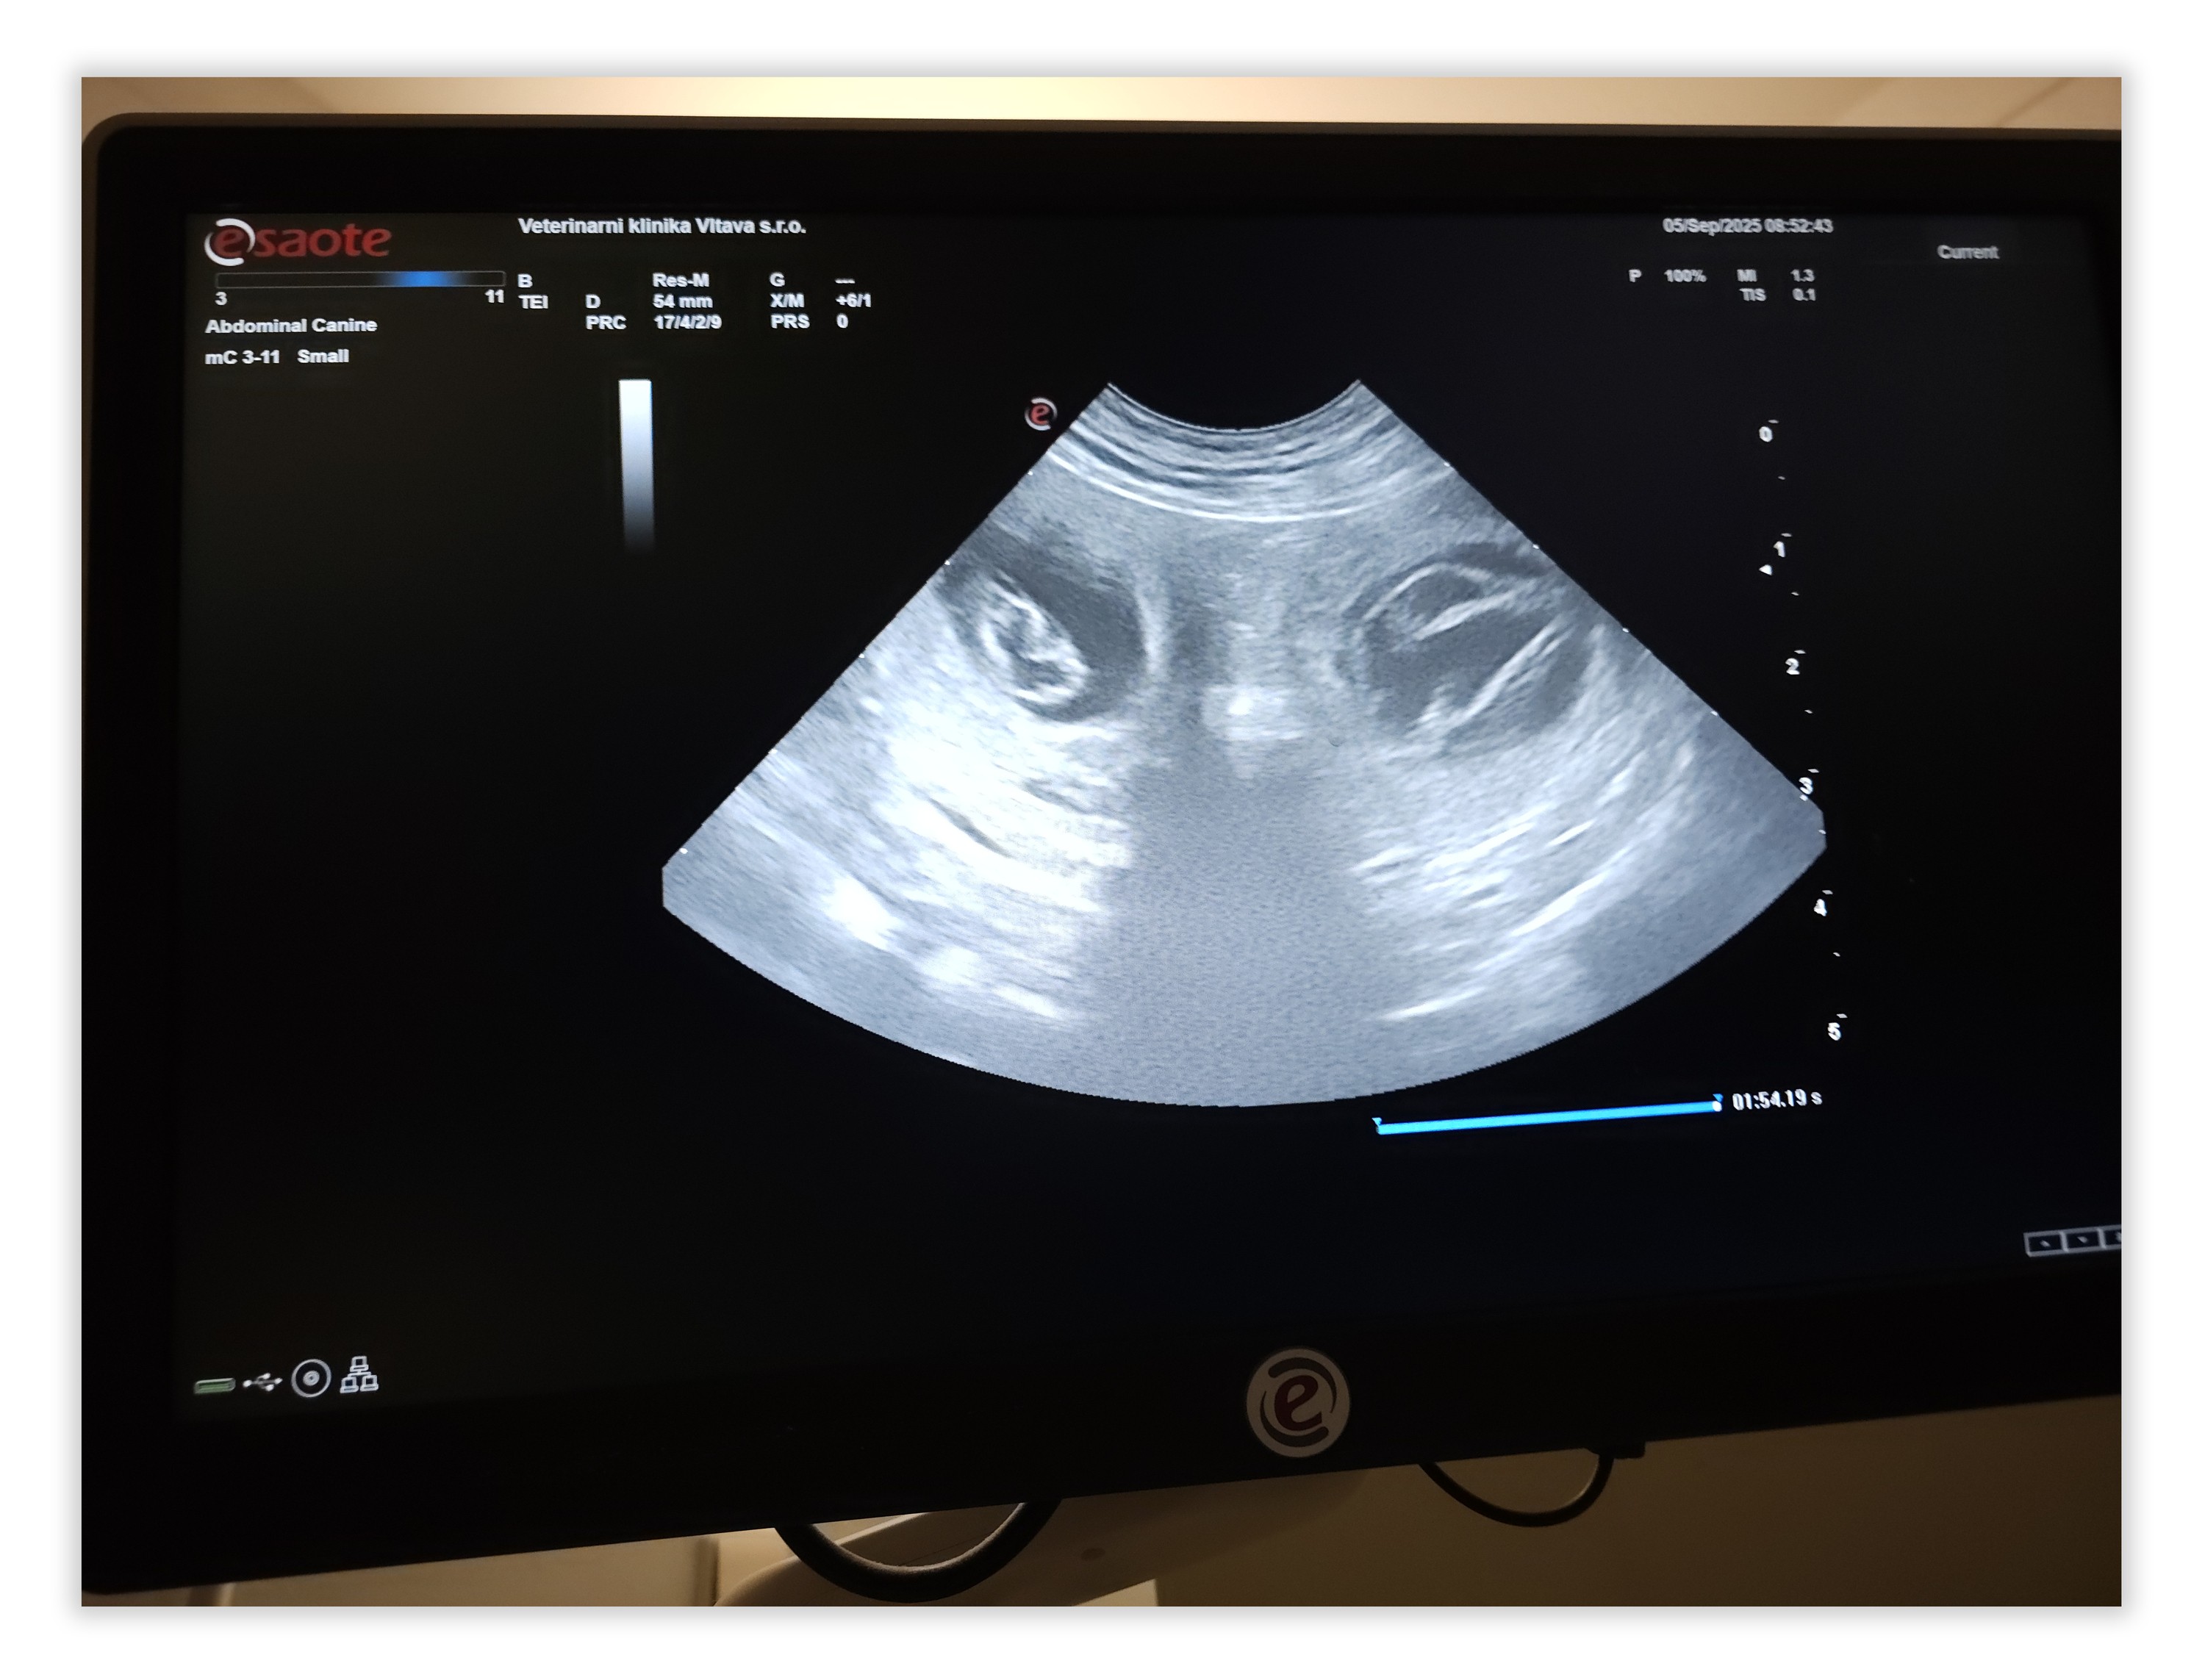

5. září 2025 - Na klinice Vltava dnes ráno potvrzena březost u Abynky! Napočítali jsme 3 kuličky na levé a 3 na pravé straně bříška. Počátkem října přivítáme na svět početný vrh "G", půjde o mladší sourozence vrhu "F", tatínkem je výstavně i lovecky veleúspěšný Joey (Fantasy Fly Jo-Bear)